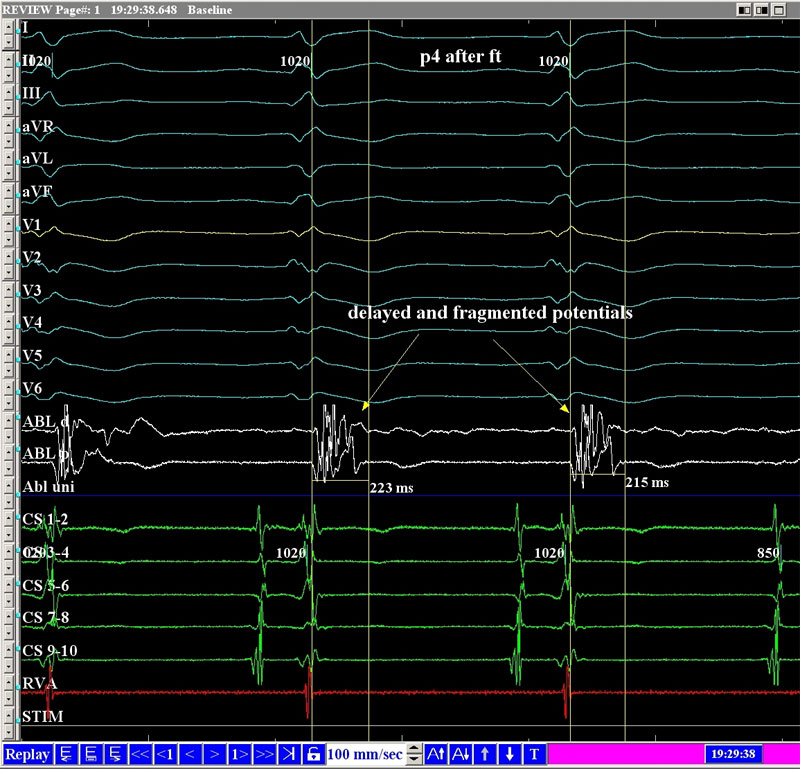

С 2021 г. в Лаборатории диагностики и лечения эпилепсии Отделения нейрохирургии стационара стали проводить радиочастотную термодеструкцию выявленных эпилептогенных очагов одновременно с проведением инвазивного стерео ЭЭГ мониторирования.

Впервые в России выполнена эпикардиальная абляция при синдроме Бругада

В Пироговском Центре создана соответствующая мировым требованиям эпилептологическая служба:

- Мультидисциплинарная команда (врачи разных специальностей, инженеры, лингвисты, математики и аналитики, специалисты IT)

- Высокотехнологичная нейрохирургическая служба

- Современная нейрофизиологическая лаборатория

- Передовая анестезиологическая служба

- Современная нейровизуализация (МРТ, ОФЭКТ, SISCOM)

Внедрен современный протокол диагностики эпилептогенных очагов головного мозга — протокол SISCOM (Subtraction Ictal SPECT Co-Registered to MRI)

Внедрение хирургического лечения эпилепсии с роботизированным инвазивным нейромониторингом